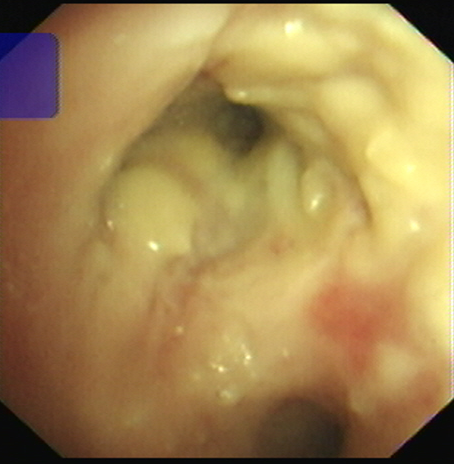

RICU陈泓主任医生阅读胸部CT,结合李女士呼吸道病毒检测提示**,根据多年临床经验指出李女士极有可能是流感后继发侵袭性肺曲霉菌病,果断经验性抗曲霉治疗,次日为李女士安排了床边气管镜检查,气管镜下见支气管管腔大量的白色膜状赘生物,管腔狭窄,它们如同顽固的藤蔓,紧紧缠绕着呼吸的通道。

▲气管镜下支气管黏膜覆盖大量脓苔,管腔狭窄